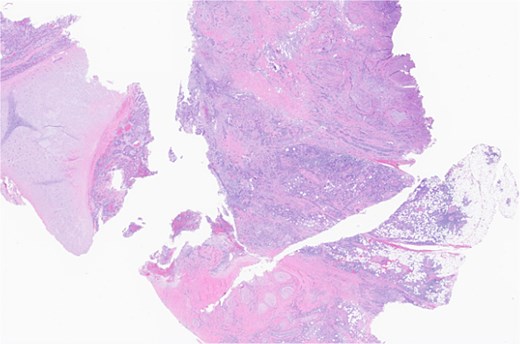

The patient underwent wide local excision of preauricular skin, parotidectomy, and selective left neck dissection (levels I–IV) (Fig. 2). Surgical pathology revealed poorly differentiated SCC involving subcutis, parotid, and surrounding soft tissues. In addition, CLL was found in three intra-parotid lymph nodes (Fig. 3). Immunohistochemistry showed cells positive for CD20, CD5, CD19, CD22, CD23, CD41, and BCL2, and negative for CD3, CD10, CD21, and cyclin D1. Flow cytometry revealed lambda light chain-restricted B-cells, with an absolute clonal B-cell count of 1.01 × 109/l, and 16.7% atypical lymphocytes in peripheral blood.

Left parotid tumor, biopsy: small lymphocytic lymphoma/CLL involving a lymph node.